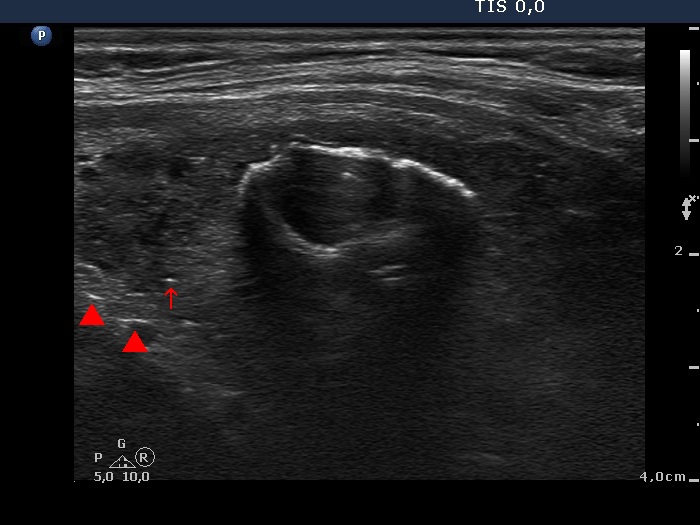

Benign hyperplastic nodule (histological diagnosis) - case cons037 |

Upper part of the right lobe |

|

The bright hyperechogenic granules (arrows) seem to be at first sight punctate echogenic foci. However, the presence of a few hyperechogenic lines (arrowheads) challenges this view: these figures might be presentations of a connective tissue.